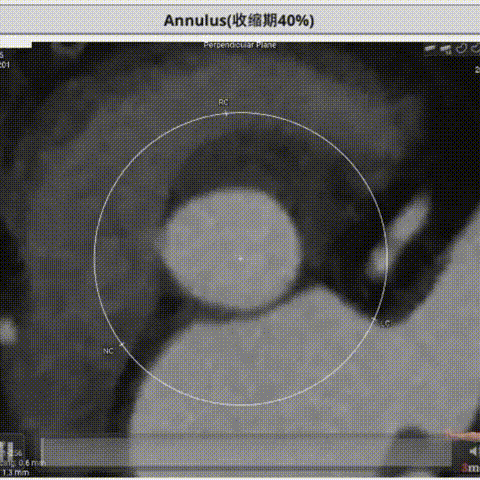

术前CT评估